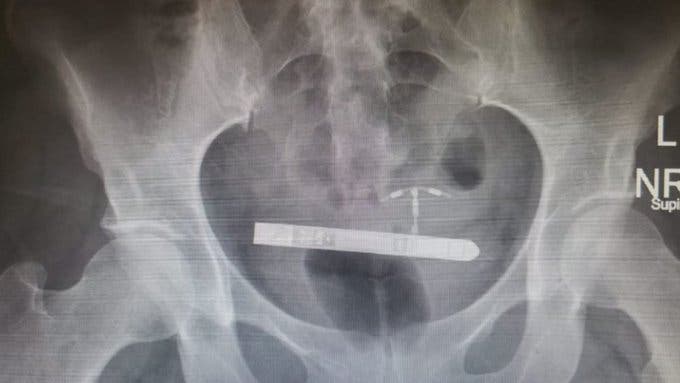

Greg Marchand, gynécologue obstétricien se souvient de l’histoire de Lauren comme une expérience inédite dans toute sa carrière. C’est lors de l’échographie qu’il s’est aperçu d’une chose incroyable, le sextoy était dans la vessie de cette femme pour qui la soirée a tourné court. « Je n’ai jamais vu un cas pareil de toute ma carrière » confie le médecin. Ni une ni deux, au bloc opératoire pour retirer cet objet intrusif. Heureusement, cette panique sera vite oubliée puisque le mini vibromasseur sera retiré de la vessie de Lauren. Plus de peur que de mal donc, pour les deux amoureux qui souhaitaient ajouter du piment à leurs ébats.